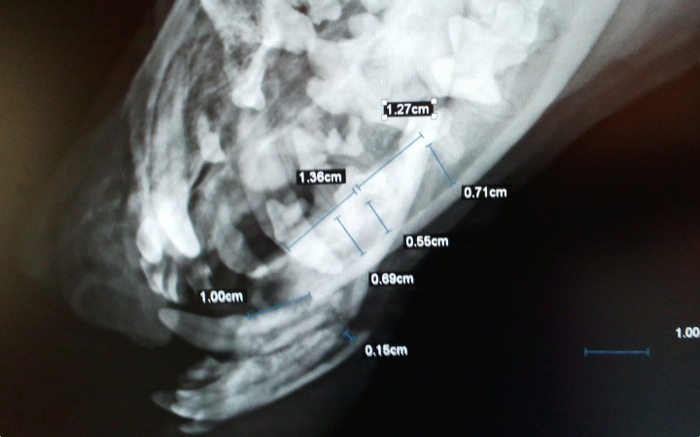

| Diagnostico | Fractura bilateral y muy rostral de mandíbula inferior. |

| Pruebas | La radiografía confirma lo que en la exploración se veía como un fragmento distal casi exento de tejido óseo donde fijar cualquier implante. |

Las medidas tomadas no ofrecen soluciones fáciles para un arreglo cómodo.

Del fragmento distal sobresalen los alveolos dentales limpiamente separados de las raíces de ambos caninos inferiores.